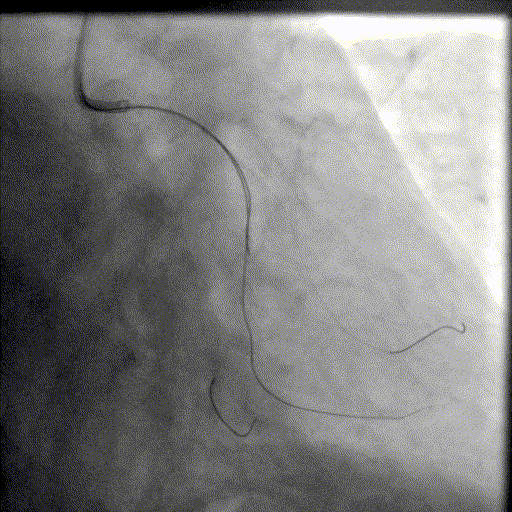

病例三

朱天奇教授

创新性二次干预:IVL修正支架植入术后贴壁不良。

基本情况:患者,男,73岁,因“活动后突发持续性胸痛”入院。既往高血压、糖尿病病史,血脂异常(LDL-C 3.94mmol/L)。

简要病史:患者曾于2025年4月因急性下壁心肌梗死,急诊行PCI治疗,于RCA植入1枚支架。本次入院计划处理LAD。

辅助检查:EKG:下壁导联Q波,T波倒置;UCG:左室下壁收缩活动减弱,LVEF 57%。

基础造影

右冠状动脉近段基本正常,中段狭窄50%,远段原支架通畅,右冠-后降支开口狭窄70%;左主干狭窄40%;前降支近中段全程弥漫性钙化病变,狭窄80-99%,第一对角支狭窄60%,第二对角支狭窄80%;回旋支近段基本正常,远段狭窄60%。

手术经过

导丝到位

当指引导管冠脉开口到位后,选择三根对应导丝分别送入LAD、D1、D2远端。

球囊预扩

选择不同尺寸的预扩球囊逐级预扩张病变,复查造影狭窄减轻不明显。为了解血管真实情况,遂启用IVUS检查。

术前腔内影像学IVUS指导

IVUS提示血管内钙化严重,最小管腔面积不足 4mm²;遂考虑启动IVL治疗。

冲击波球囊治疗

2.5*12mm@4atm 冠脉血管内冲击波导管反复进行8个周期治疗,经IVUS检查提示最小管腔面积增加至4.88mm²;随后选取后扩张球囊对病变行扩张治疗。

支架植入并后扩

于LM-LAD依次植入两枚药物洗脱支架,经非顺应性球囊后扩张支架,复查造影&IVUS提示血管内钙化仍较重,支架贴壁不良,遂再次启动IVL治疗。

再次冲击波球囊治疗

3.0*12mm@4atm 冠脉血管内冲击波导管反复进行5个周期治疗,并选取后扩张球囊对病变行扩张治疗。最终复查造影提示残余狭窄小于10%,未见夹层及血肿,TIMI血流3级。